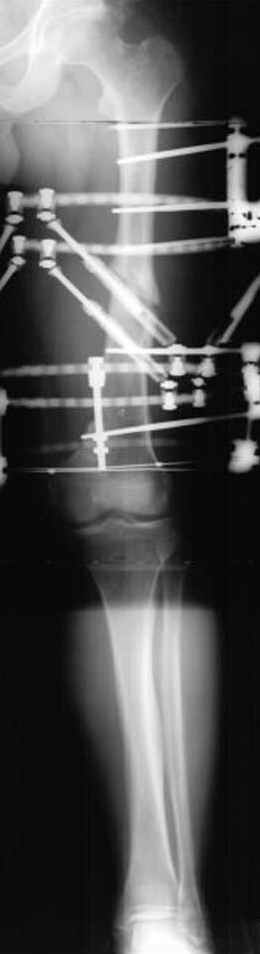

N3 рисунок окончательный снимок, после операции моя рентгенограмма должен выглядеть примерно как эта картина. На N4 снимке клин перед удалением; N5 послеоперации 3 нед.; N6 окончательная рентгенограмма.

пластическая модель; и коррекция бедра аппаратом Илизарова.